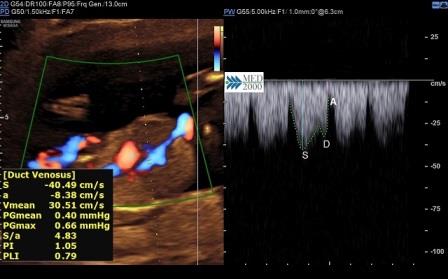

Dotto Venoso

Il razionale dello studio del flusso nel dotto venoso è legato al fatto che nei feti con anomalie cromosomiche e con malformazioni cardiache si può avere una inversione dell'onda relativa alla contrazione atriale (onda A). L'inversione dell'onda A nel dotto venoso si riscontra nel 65% dei feti affetti da Trisomia 21. Normalmente l'onda flussimetrica caratteristica del dotto venoso è rappresentata da:

- onda S caratteristica delle sistole ventricolare

- onda D caratteristica della fase protodiastolica

- onda A caratteristica delle contrazione atriale

Un'onda A invertita si associa ad un rischio elevato per:

- anomalie cromosomiche

- cardiopatie congenite

- morte fetale

Tuttavia in circa l'80% dei casi in cui l'onda A è invertita l'outcome della gravidanza è normale.

La valutazione del flusso nel dotto venoso migliora l'efficacia dello screening combinato aumentando la sensibilità dal 90% al 95% con una riduzione della percentuale di falsi positivi dal 3% al 2,5%.

Lo studio del flusso nel dotto venoso e del flusso della tricuspide possono essere utilizzati nei feti con NT aumentata (spessore > 3,5 mm.) e cariotipo normale per identificare i casi che necessitano di controlli più frequenti per il rischio di cardiopatie congenite.